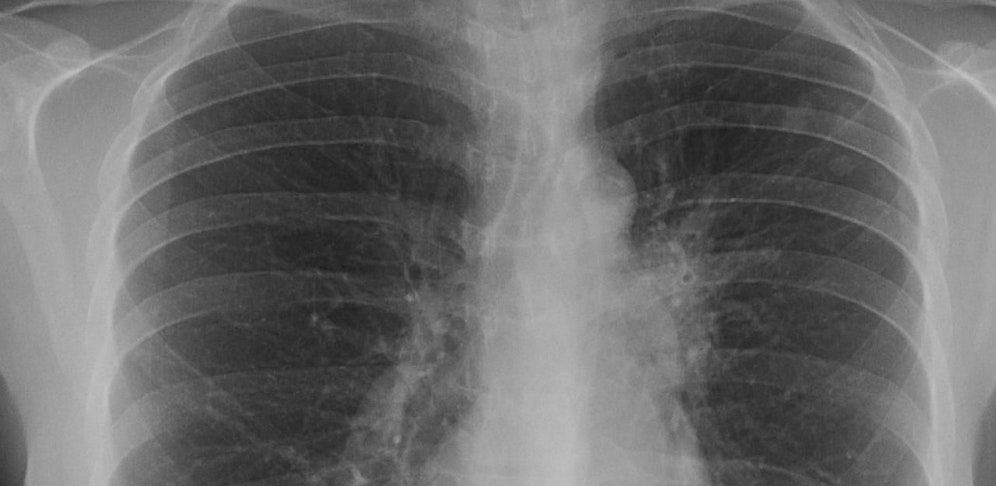

Der Röntgenbus des Landes Niederösterreich komme am Mittwoch zum Gymnasium, hieß es. Untersucht werden demnach die Klassenkameraden des erkrankten Schülers sowie Kinder, die gemeinsamen Turnunterricht mit dem Buben hatten.